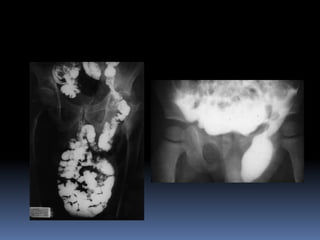

DIAGNOSTICO.  Historia Clinicay Examen Fisico.  Diagnosticos diferenciales: •Procesos inflamatorios: abscesos, aductores, cadera •Procesos neoplásicos: adenopatias metastásicas •Patología testicular: epididimitis, hidrocele, quiste de cordon, varicocele •Patología vascular: aneurisma de laV.safena

• 23.